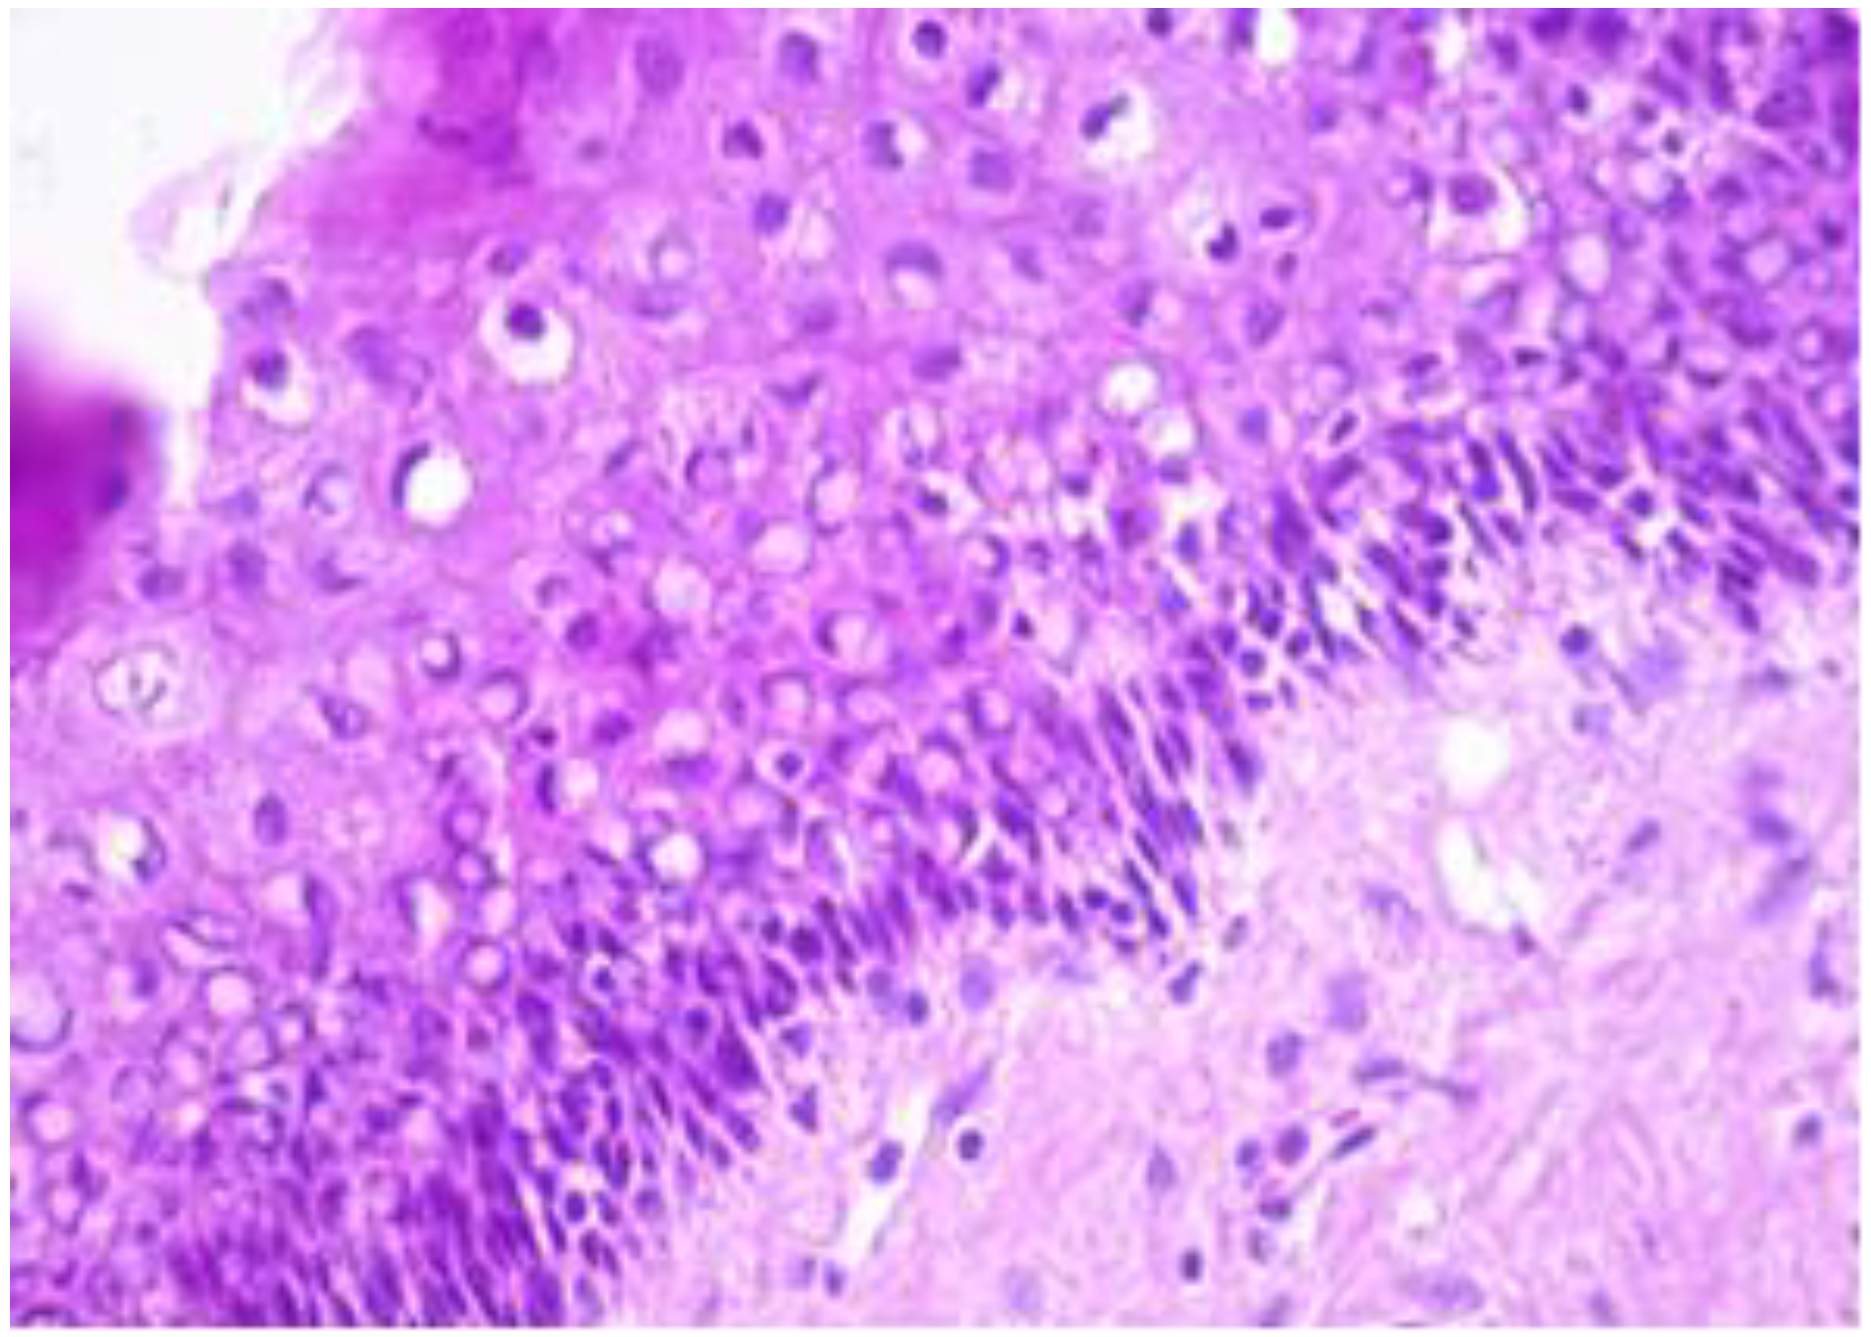

Structure And Histology Of The Cervical TZ. A. Schematic Representation

histology cervical cervix tz endocervix ectocervix epithelium squamous representation glands metaplasia nabothian tissue